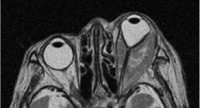

IgG4関連疾患とは、血清IgG4が上昇し、全身の諸臓器にリンパ形質細胞浸潤病変を呈する疾患概念です。眼科領域ではIgG4関連涙腺炎が代表的な病態です。(図は本疾患のMRI:Takahira et al. Arch Ophthalmol 125:1577-, 2007 から引用)。IgG4陽性病変は涙腺以外の眼窩組織にもみられ、視神経症による視力低下をきたす重症例もあります。またIgG4関連眼疾患ではときにリンパ腫を併発するので、その鑑別診断は重要です。